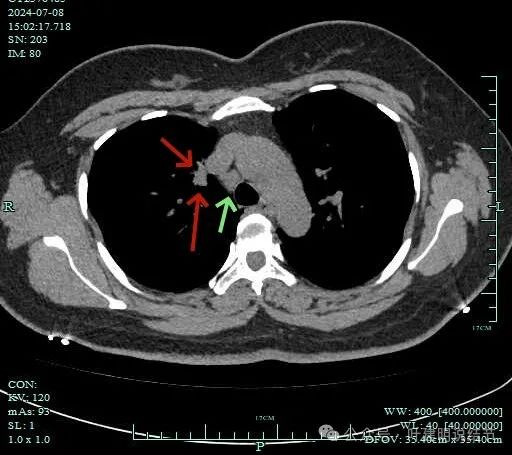

再看2024年7月份的影像:

病灶有血管与之相连,淋巴结更显得明显了。

肺窗上见与上腔静脉紧贴着,病灶边缘稍显模糊。

病灶边上不清爽。

病灶有毛刺与小棘突征,有邻近细支气管扩张,表面不平,膨胀性不明显。